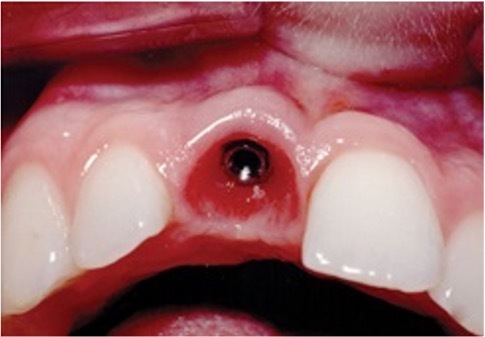

21

Q

What condition is shown here?

A

Advanced periimplantitis